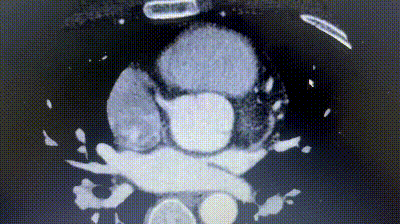

2. Il CTA coronarico ha rivelato un'origine anomala dell'arteria circonflessa sinistra (LCX) dal seno coronarico destro, con un decorso tra l'aorta e l'atrio sinistro.

3. La distanza tra l'ASD e l'aberrante LCX era solo di circa 6mm.